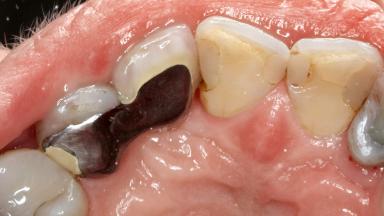

Surgical Management of Peri-Implantitis: Removal of Implant Due to Recurrent Infection Using an Implant-Retrieval Tool

A 65-year-old female patient was referred to the periodontist for assessment and management of infection associated with an implant at site 12. The general dentist had noted suppuration on probing during examination.